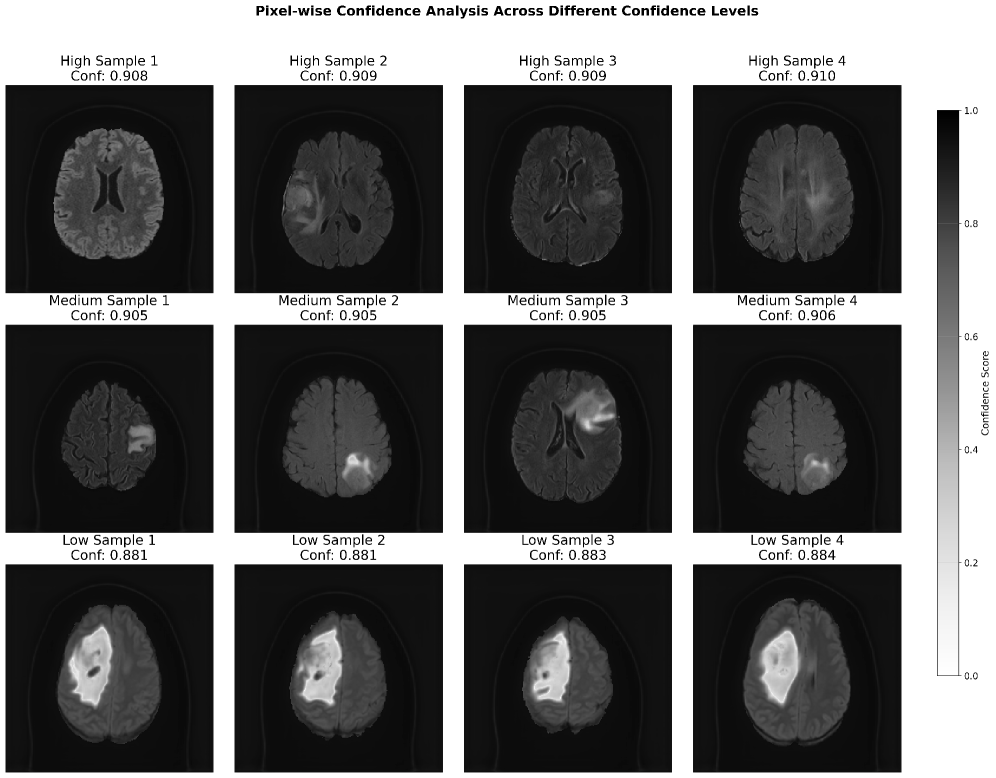

Figure 9 illustrates pixel-wise prediction confidence maps for a set of segmentation outputs, stratified by overall confidence levels—high, medium, and low. Each row contains four representative MRI slices from each confidence tier, with the corresponding average confidence score annotated above each sample.

Refer to caption

Figure 9: Pixel-wise confidence stratification across brain MRI samples categorized by prediction confidence levels. Three rows display high (0.908-0.910), medium (0.905-0.906), and low (0.881-0.884) confidence predictions, each with four representative slices and annotated mean scores. Grayscale colorbar indicates confidence intensity. High-confidence samples exhibit uniform lesion boundaries, while low-confidence samples show heterogeneous patterns, demonstrating spatially-resolved uncertainty estimation for selective prediction use.

The figure9 presents a grid of brain MRI scans arranged to analyze pixel-wise confidence levels across different samples with varying confidence scores. The rows represent samples categorized into high, medium, and low confidence levels, with corresponding confidence values noted beneath each image. The high-confidence samples (first row) exhibit confidence scores ranging from 0.908 to 0.910, while the medium-confidence samples (second row) range from 0.905 to 0.906, and the low-confidence samples (third row) vary from 0.881 to 0.884. A grayscale color bar on the right indicates the confidence score, with lighter regions in the scans suggesting areas of higher confidence. The visualization highlights the spatial distribution of confidence scores and how these vary across different samples, providing insights into the pixel-level confidence variability within the MRI images. The overall layout emphasizes differences between confidence levels while maintaining consistency in the display format for comparison.